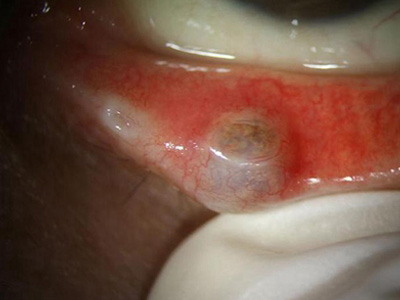

睑板腺癌症状图片

肿块继续增大后可在结膜面上透见黄色,结节表面不平,继而形成溃疡,出现菜花样肿块,触之易出血,分化程度较低者通过淋巴管可以较早地向耳前淋巴结和颌下淋巴结转移。